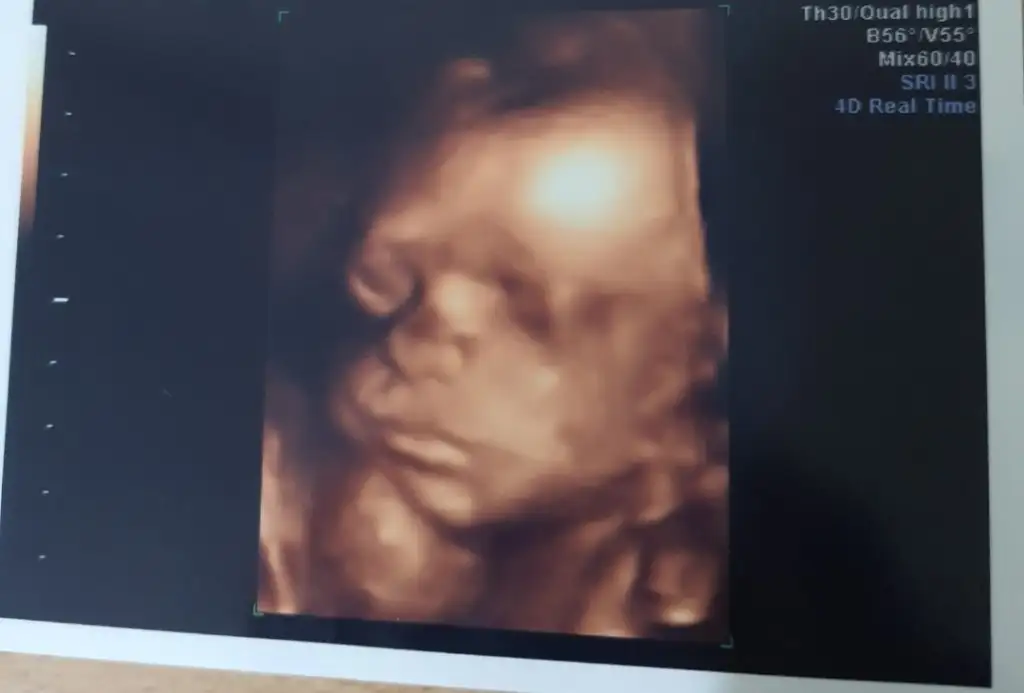

Slmlar herkese bizim bugun doktor ziyaret günümüzdu tam 26+0 810 grm 32 santimmisiz kafası sağ kaburgamın altindaymis ters duruyo dedi böbrek ağrın olursa panik yapma dedi bebis hep bi yerdeymis çünkü bu da resmimiz💕

• Screenshot_20220416-191945_Gallery.webp

Screenshot_20220416-191945_Gallery.webp

11,7 KB · Görüntüleme: 110

• Screenshot_20220416-191852_Gallery.webp

Screenshot_20220416-191852_Gallery.webp

11 KB · Görüntüleme: 105